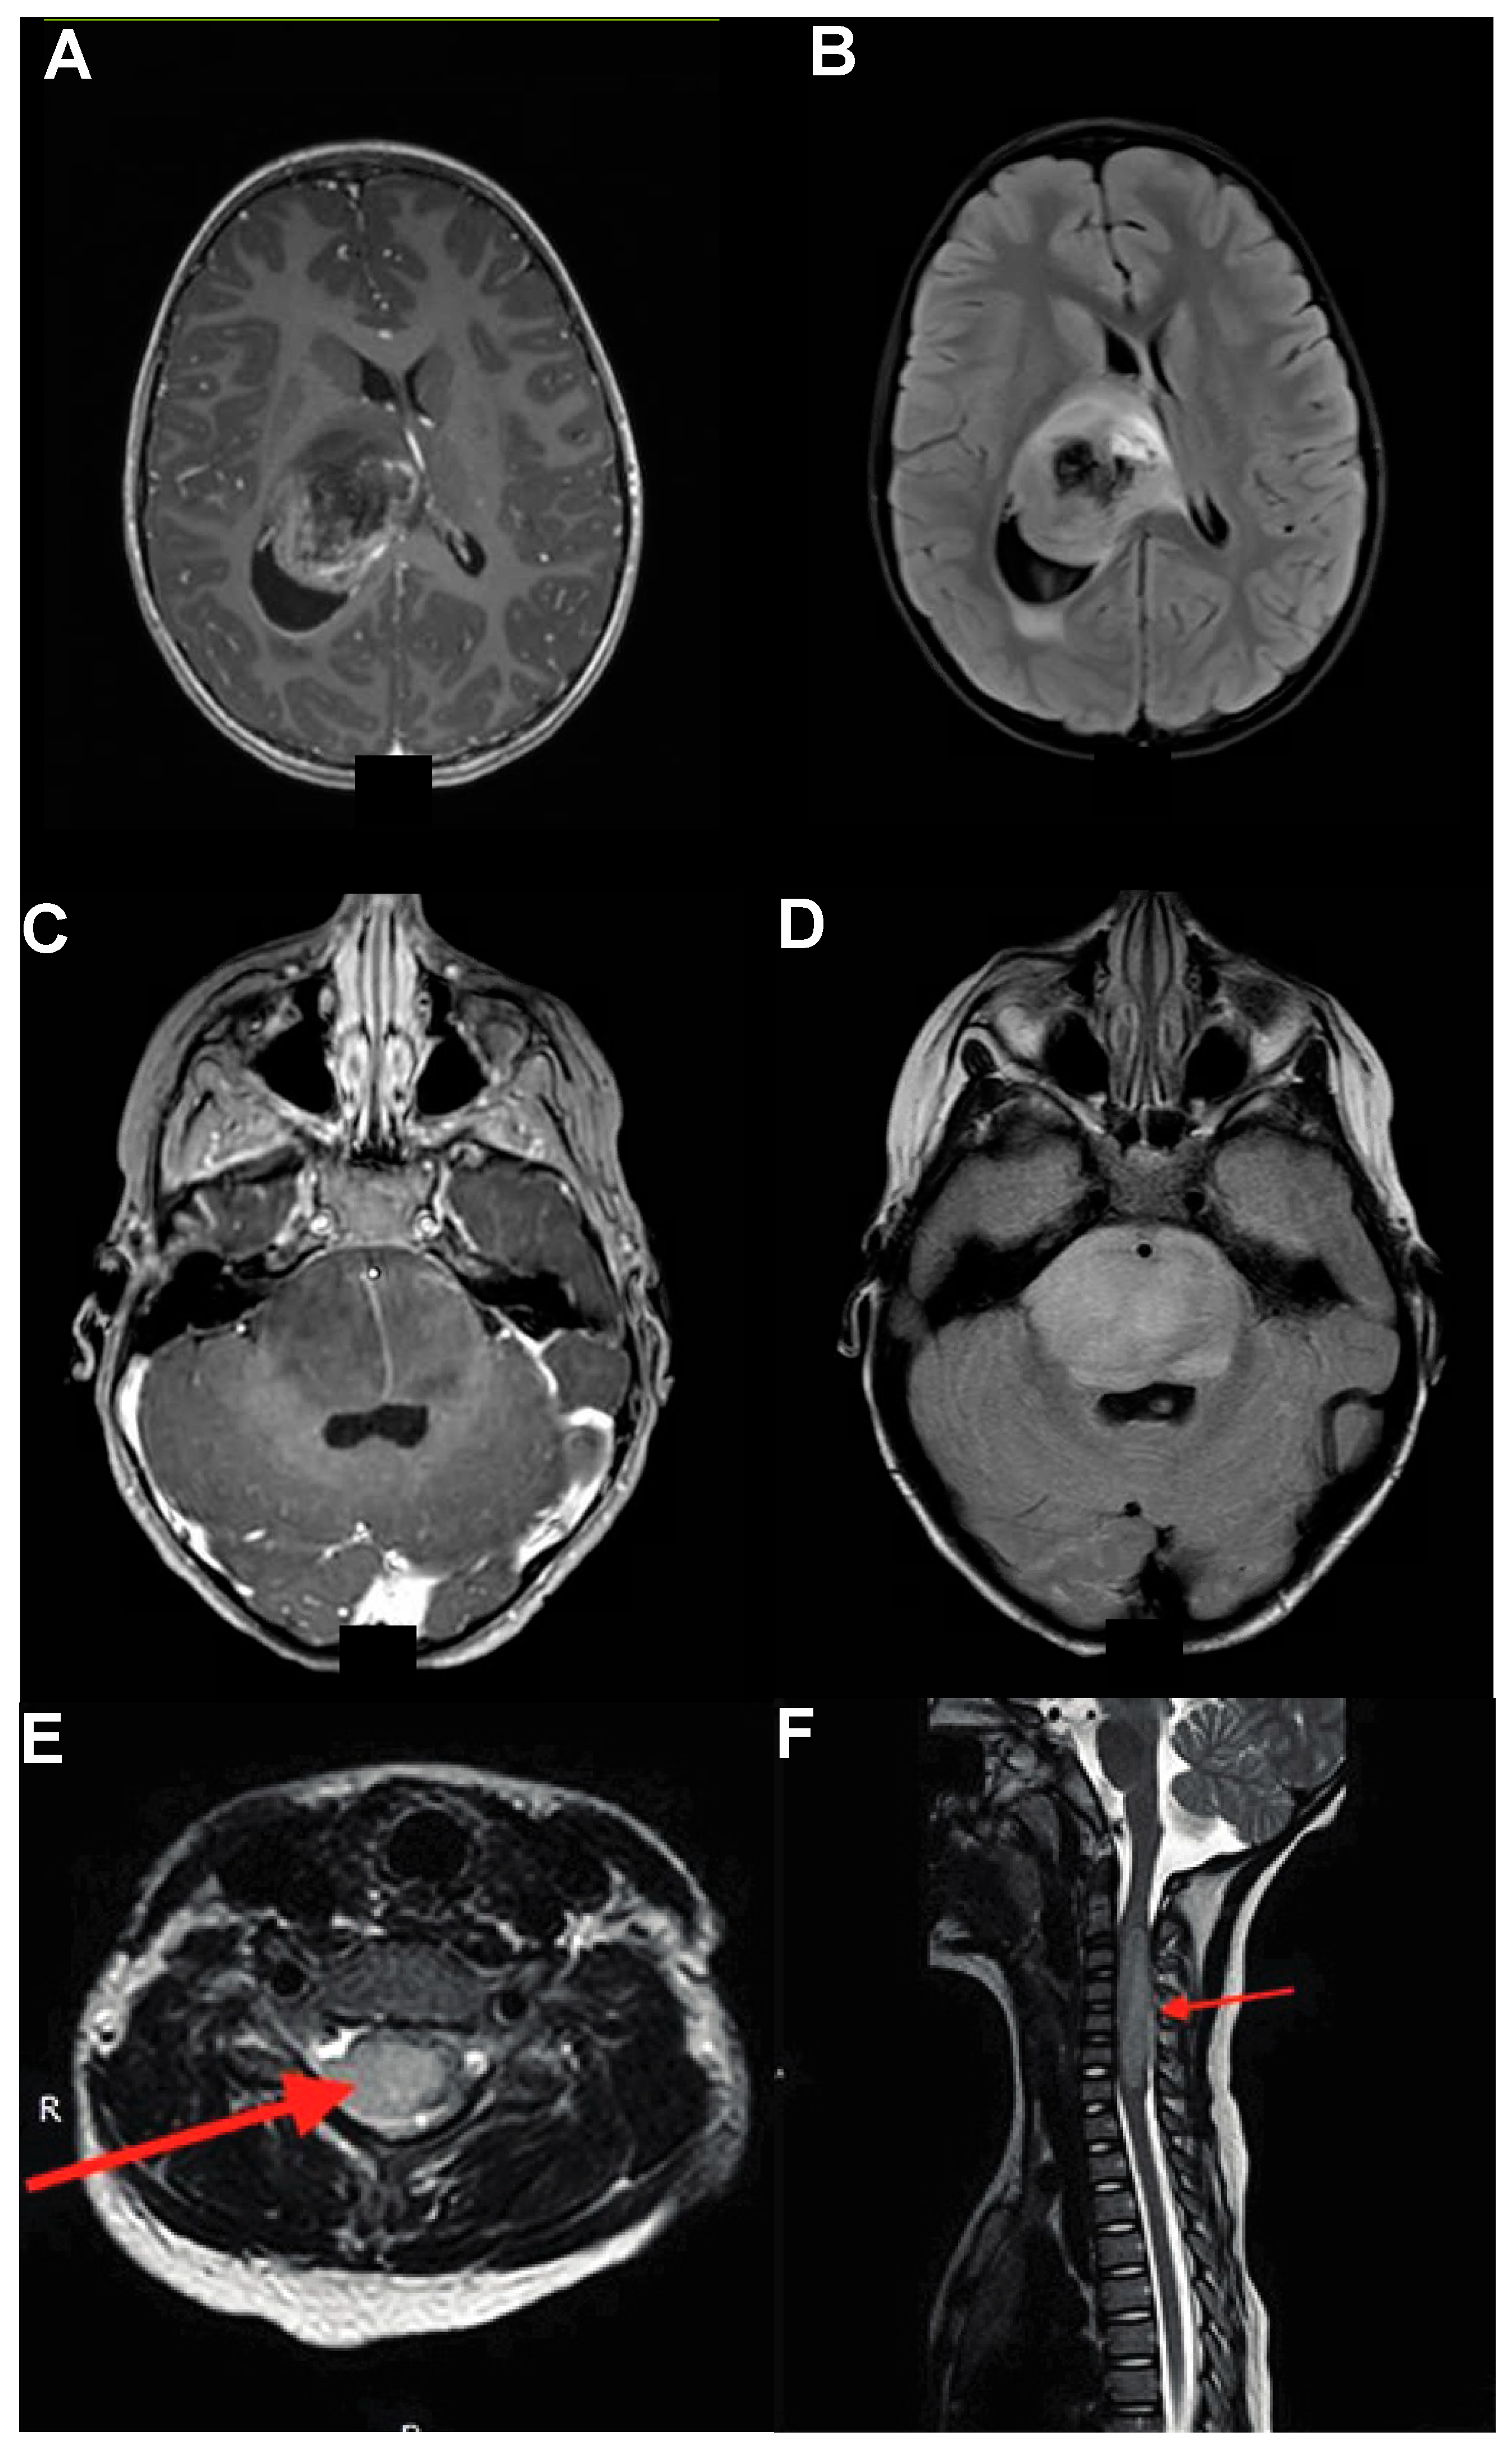

Given the wide variety of anatomical locations and presentations, it logically follows that DMGs have a complex appearance on MRI, the main modality of imaging (CT, owing to its lower tissue resolution, is not part of standard clinical practice except as a first-line screening tool). Prior to biopsy, a presumptive diagnosis is usually made, then confirmed with tissue sampling, given imaging features different from other pathologies often found in these locations [1,20,21]. It is important to note how DMGs are famous for their occasionally heterogenous radiographic and MRI appearances, with more than one expert practitioner challenged by unusual imaging characteristics. At the same time, separating DMGs from other clinical entities remains essential, given the diametrically opposed treatment algorithms available for other tumor types. With this being said, in general, thalamic gliomas usually present as a thalamic-centered lesion (unilateral or bilateral); contrast enhancement is common but not universal, heterogenous, and not well circumscribed, unlike other low-grade gliomas (e.g., pilocytic, not H3.3K27M mutated) (Figure 2A). Locoregional mass effect on the internal capsule or third or lateral ventricle, diffusion restriction on diffusion-weighed imaging, and tumor-associated edema (seen as FLAIR signal) are often seen as well (Figure 2B) [19,22,23].

Midbrain DMGs rest on the same spectrum as DIPGs: in cases of infiltrative lesions, the border between the midbrain and pons is often blurred, with lesions crossing the superior pontine sulcus with an inferior trajectory (if arising in the midbrain proper) or a superior one (if from the pons). Radiographically, these tumors share common features, such as an enlargement of the native cytoarchitecture (for DIPG, upwards of 50% of the pons), a wispy, non-capsular gadolinium enhancement, and a significant FLAIR signal that often extends beyond the contrast-enhancement pattern (Figure 2C,D) [24,25]. Importantly, dichotomizing FLAIR signal into tumor proper and reactive inflammation without obvious tumor cells has been a challenge and the matter of much research aimed at defining better biopsy targets [26,27]. Albeit the subject of much research, this matter is yet to be put to rest: novel imaging modalities are emerging in an effort to answer this question, but to date, biopsy can be the only definitive diagnostic. Importantly, DMGs can be differentiated from other (more benign) pontine lesions, such as tectal gliomas and dorsal exophytic tumors. Tectal gliomas tend to have a growth pattern restricted to the tectal plate, without contrast enhancement; dorsal exophytic tumors, as the name suggests, present as exophytic growths from the pontine trunk, with a clearly demarcated border separating them from the brainstem.

Spinal DMGs share features with their cranial counterparts, with growth patterns logically restricted by the limited axial spread possible within the spinal cord; thus, these lesions have a predominant rostro-caudal elongation rather than anterior–posterior or medio-lateral one. They are characterized by a significant FLAIR signal often spanning multiple spinal levels and poorly differentiated contrast enhancement (Figure 2E,F) [28,29]. Spinal DMGs can be difficult to distinguish from other astrocytic spinal lesions; these tend to be more eccentric and can have stronger contrast enhancement, albeit the two entities can be difficult to separate by MRI alone [30].

Figure 2.

DMGs Imaging Characteristics. (A,B) Thalamic gliomas show involvement of various thalamic nuclei (A) and a significant FLAIR signal (B) causing locoregional mass effect, ventricular entrapment, and internal capsule involvement. (C,D) DIPG and midbrain DMGs are characterized by wispy heterogeneous contrast enhancement (C) and enlargement of the pons (D). (E,F) Spinal gliomas, like their cranial counterparts, are characterized by heterogenous contrast enhancement (E), with significant cranio-caudal spread (F). Adapted from [31].